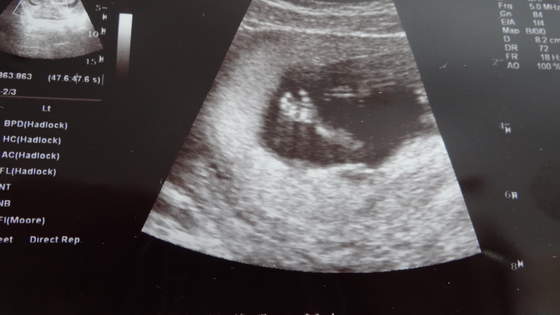

No i zerkamy na płeć (of kors nic nie mówiłam, że tydzień temu byłam gdzie indziej i lekarka sugerowała, że to mógłby być chłopiec). A gin mówi, że na 95% dziewczynka

No i rzeczywiście, już żadnego cypelka nie widać!!! A podobieństwo tego obrazu do tego jak dowiedzieliśmy się w I ciąży, że będzie dziewczynka uderzające!!! Wow, ale byłoby super! Szczególnie, że marzyliśmy o drugiej dziewczynce.